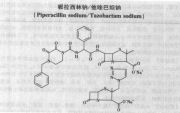

| 2021年7月26日 (一) 20:01 | 哌拉西林钠他唑巴坦钠.jpg (文件) |  |

65 KB | 77921020 | Uploaded with SimpleBatchUpload | 3 |